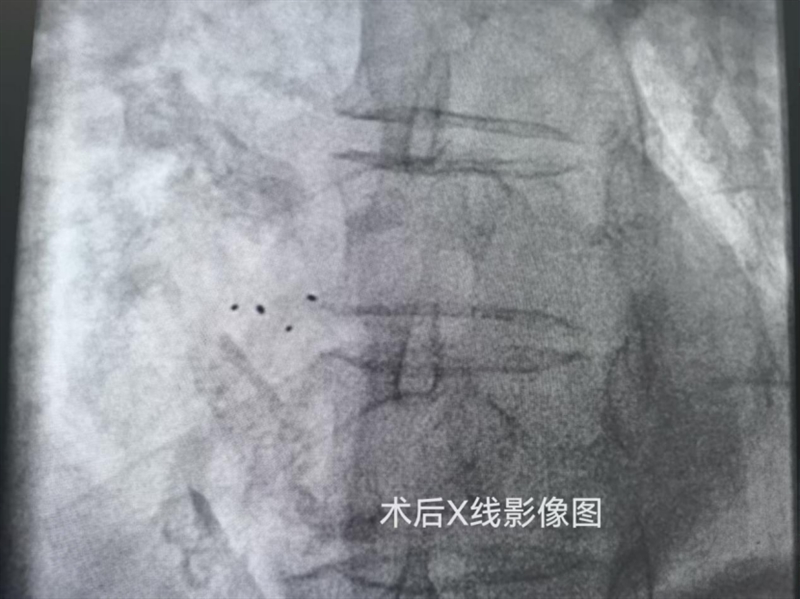

技术突破的背后,是医者对“敬佑生命”的坚守。可降解封堵器手术难度远超传统术式——它在X光下不可见,全凭医生凭借解剖经验和手感,通过四个铂金标记点精准定位。“就像在‘盲操作’中凭手感和解剖经验精准放置,每一步都得反复确认。”陈运清主任团队术前反复模拟手感,术中结合超声与X光双重验证,最终仅用半小时就完成了核心操作。虽然比传统手术需要更多的谨慎,但成功率与金属封堵器相当,患者术后即刻就能感受到症状改善。